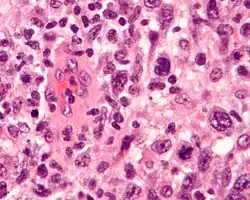

| Micrograph of an anaplastic large-cell lymphoma. H&E stain. | |

ALCL is defined based on microscopic histopathological examination of involved tissues which shows the presence of at least some ALCL-defining pleomorphic cells. These "hallmark" cells have abnormal kidney-shaped or horseshoe-shaped nuclei, prominent Golgi, and express the CD30 tumor marker protein on their surface membranes.[4] In 2016, the World Health Organization (WHO) separated ALCL into four types: ALK-positive ALCL (also termed ALK+ ALCL), ALK-negative ALCL (ALK− ALCL), primary cutaneous ALCL (pcALCL), and breast implant-associated ALCL (BIA-ALCL). WHO defined BIA-ALCL as an ALCL type provisionally, i.e. subject to redefinition if future studies should support such a change.[4][5]

ALK-positive ALCL is diagnosed by histological and immunological examinations of involved tissues, typically lymph nodes. These tissues have lymphoma-like infiltrates that have variable numbers of ALCL "hallmark" cells, i.e. cells with kidney- or horseshoe-shaped nuclei that strongly express CD30 as detected by immunohistochemistry and an ALK fusion protein as detected by fluorescence in situ hybridization.[11] These cells are scattered throughout the infiltrates. WHO classifies these infiltrates into 5 patterns: a common pattern consisting of large variably shaped cells with large nuclei that typically contain multiple nucleoli (60–70% of cases); a small-cell pattern consisting of small to medium-sized neoplastic cells with clear cytoplasm and "hallmark" cells that are concentrated around small blood vessels (5–10% of cases); a lymphohistiocytic pattern consisting of small neoplastic cells along with abundant histiocytes (10% of cases); a Hodgkin's-like pattern in which the architecture resembles the nodular sclerosis pattern of Hodgkin lymphoma (3% of cases); and a composite pattern consisting of two or more of the just described patterns (15% of cases).[9] Detection of circulating autoantibody against ALK supports the diagnosis.[10] Individuals with low levels of these autoantibodies are at an increase risk of relapsing after treatment.[9]

The histology of ALK-negative ALCL, similar to ALK-positive ALCL, consist of "hallmark" cells that strongly express CD30. Unlike ALK-positive ALCL, however, ALK-negative ALC does not fall into different morphological patterns. The histological of this disease may overlap with and be difficult to distinguish from other CD30-positive T-cell lymphomas or the nodular sclerosis form of Hodgkin lymphoma. Cases in which ALK-negative ALCL is not distinguishable from the latter lymphomas are best diagnosed as peripheral T-cell lymphoma not otherwise specified (PTL, NOS). The histology of ALK-negative ALCL may also overlap with tumors of non–T-cell lineage such as various carcinomas. The differential diagnoses of ambiguous cases may be helped by examining the tumor cells for the expression of certain marker proteins. For example, expression of CD56, MUC1 (also termed EMA for epithelial membrane antigen), and clusterin and strong uniform expression of CD30 support the diagnosis of ALK-negative ALCL over PTL, NOS, while variable CD30 expression and extensive expression of T-cell receptor proteins favor PTCL-NOS over ALK-negative ALCL. Detection of certain gene abnormalities (see next section) may also help distinguishing these diseases.[4]

Diagnosis

In most individuals with BIA-ALCL, the affected breast has a thickened capsule around the implant and effusion fluid between the capsule and implant. Neoplastic cells are located in and typically limited to the capsule and effusion. Histological examination of the capsules shows large anaplastic cells but cells with all the features of ALCL "hallmark" are often difficult to detect. In addition to these neoplastic cells, the capsule lesions contain, sometimes in a large excess that makes diagnosis difficult, a variety of non-malignant cells such as small lymphocytes, histiocytes, and granulocytes (the granulocytes are mostly eosinophils). The histology of palpable masses exhibit a different pathological picture: the tumor masses have multinodular areas that consist of necrosis or fibrous tissue interspaced with areas that consist of large neoplastic cells that have abundant cytoplasm and abnormally shaped nuclei within a fibrotic and chronic inflammatory cell background. Again, typical ALCL-defining "hallmark" cells may be difficult to find in these masses. The effusions show abundant, uniform-appearing, non-cohesive large cells with irregularly-shaped nuclei, prominent nucleoli and abundant cytoplasm.[27] The histology and pathological features of diseased lymph nodes and tissues outside of the breast implant are indistinguishable from those seen in ALK-negative ALCL. The neoplastic cells in the capsules, effusions, and tissues strongly and uniformly express CD30, CD4 (75–84% of cases), EMA (48–90%), CD43 (86–95%), CD45 (44–74%), and in a far fewer percentage of cases various other marker proteins. These cells do not express ALK and often lack the characteristic surface marker proteins of T-cells. Identification of the status of these markers helps diagnose the disease.[4]